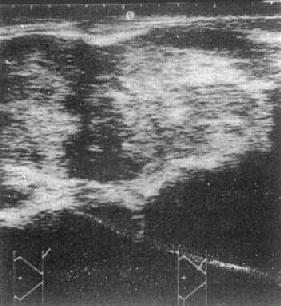

1.肾癌 USG可见肾增大、形态异常,肿瘤呈实质性暗区,其内可有细小、散在、分布均匀的光点,肿瘤侧壁出现边界不清的低回声带,肿瘤内出血、坏死、液化则出现液性暗区。肾盂、肾盏因受肿块推压,致其光点移位,甚至消失(图4-4-5)。血管内瘤栓形成散在或稀疏的血管内回声;肾门淋巴结增大则呈类圆实质性低回声区环绕肾蒂及主动脉与肾动脉的连接部;主动脉旁淋巴结增大,使大血管轮廓不清,或于腹膜后中线部出现实质性肿块,这些对肾癌的分期十分重要。肾癌术后USG检查是肿瘤复发及局部淋巴结转移的有效诊断方法。

图4-4-5 左肾癌

左肾大部被混杂回声肿物占据,

内部回声不均,边界不清